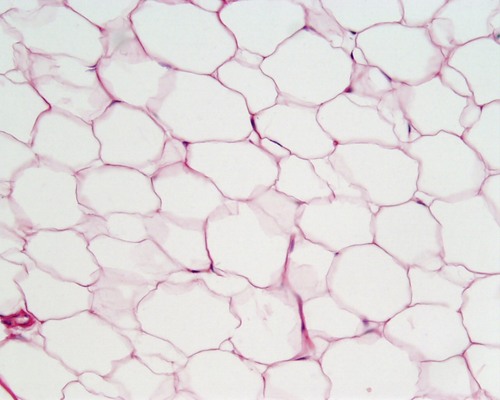

adipose

cushions, insulated and stores energy